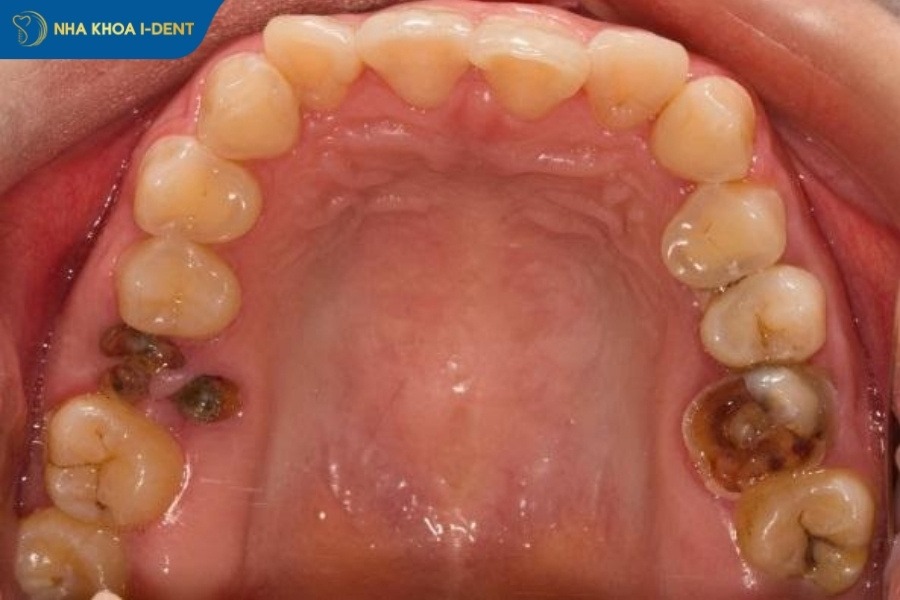

Các trường hợp răng sâu cần nhổ răng được bác sĩ chỉ định gồm:

- Răng sâu hoàn toàn: Vi khuẩn sâu răng tấn công và phá hủy toàn bộ mô răng, gây viêm tủy và vùng quanh chóp răng. Lúc này, việc nhổ răng sẽ ngăn chặn cơn đau và ngăn lan rộng ra các vùng khác.

Răng sâu hoàn toàn cần nhổ bỏ để ngăn chặn cơn đau và các biến chứng khác.